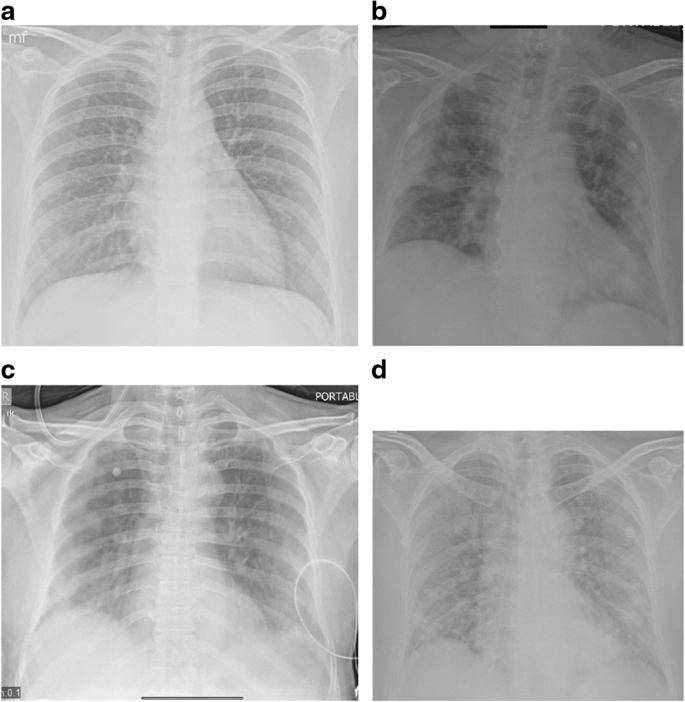

Fig. 2

figure 2

Chest X-ray AP portable in 2 patients showing radiological progression. Technical factors: 70kV and 20 mAs. Images a and b show generalized confluent consolidation of both lungs on a background of ground glass haziness with additional features of pneumothorax and pneumomediastinum. Images c and d show bilateral intercostal drains for pneumothorax and extensive subcutaneous emphysema. An additional feature of pneumomediastinum is also seen in image d

Sixty percent of the total X-rays were abnormal and showed unilateral or bilateral lung manifestations which included ground glass opacification, peripheral lung opacities, confluent consolidation, and reticular or small irregular opacities (Table 1). Additional features such as pneumothorax, pneumomediastinum, pleural effusion, and adenopathy were seen uncommonly. GGO (Fig. 1), either unilateral or bilateral, appeared most frequently in the abnormal X-rays (75% of abnormal x rays). In 81% of the 269 X-rays which showed GGO, GGO was an exclusive finding. PLO (Fig. 1) was next in frequency of appearance and seen in 88 X-rays (25%). Confluent consolidation (Figs. 1 and 2) was seen in 15% of the chest X-rays with findings. Pneumothorax and pneumomediastinum (Fig. 2) were present in only 3 out of the abnormal 358 X-rays (< 1%), as were pleural effusions. Adenopathy was not present in any chest X-ray.

Subcutaneous emphysema, pneumothorax, or mediastinal emphysema, either spontaneous or after intubation in the setting of COVID-19 infection, has been described [6, 7]. Our study included 2 cases with pneumothorax and 1 with associated pneumomediastinum after intervention. No X-rays showed adenopathy, and only 1 showed pleural effusion.